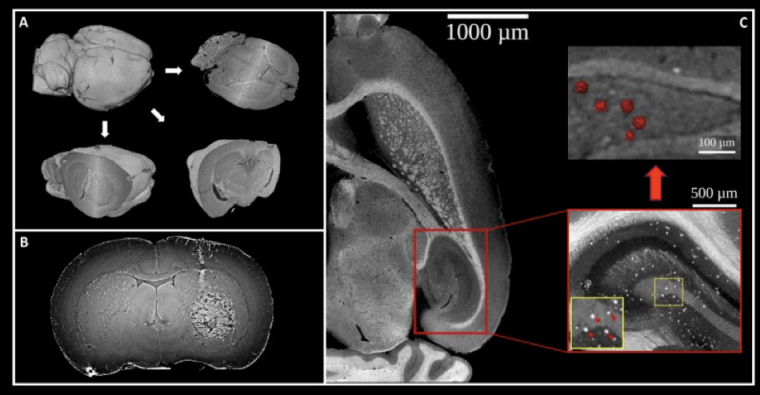

L’imagerie en contraste de phase fournit des images tridimensionnelles du cerveau qui offrent une résolution et un contraste proches de l’histologie. Ces acquisitions sont réalisées sur l’organe isolé et fixé chimiquement, comme lors d’une biopsie ou d’une autopsie. Mais l’échantillon n’a pas besoin d’être sectionné comme pour une analyse histologique : il est « numérisé en trois dimensions », et peut-être examiné sous tous les angles : l’histologie est « virtuelle » (Figures 7A et 8).

La figure 7 montre des exemples d’images, sur des modèles animaux de tumeur cérébrale (image B) et de maladie d’Alzheimer (image C). L’intérêt principal est l’étude de la morphométrie (géométrie 3D) des objets pathologiques (la tumeur, les plaques amyloïdes), qui est rendue possible, car l’organe a été scanné sans être altéré.

A. Découpe virtuelle de l’échantillon biologique « numérisé ».

B. Exemple de tumeur cérébrale implantée.

C. Étude des plaques amyloïdes dans un modèle génétique de maladie d’Alzheimer : la zone pathologique, riche en plaques amyloïdes est repérée par le rectangle rouge, les plaques apparaissent comme des points brillants qui peuvent être précisément délimités pour étudier leur géométrie en 3D.

Crédits des images : (A) Matthieu Chourrout, (B) Ludovic Broche, (C) modifiée d’après Chourrout et coll., 2021, bioRxiv.